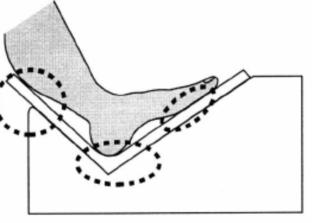

二、跟骨骨密度儀檢測時足和身體的位置

檢測時,足緊貼于產品的最下端(如圖緊貼3個部位)。 骨密度儀的護腿板與足軸和身體的中心軸,需呈一條直線。

跟骨骨密度檢測不正確坐姿示意圖